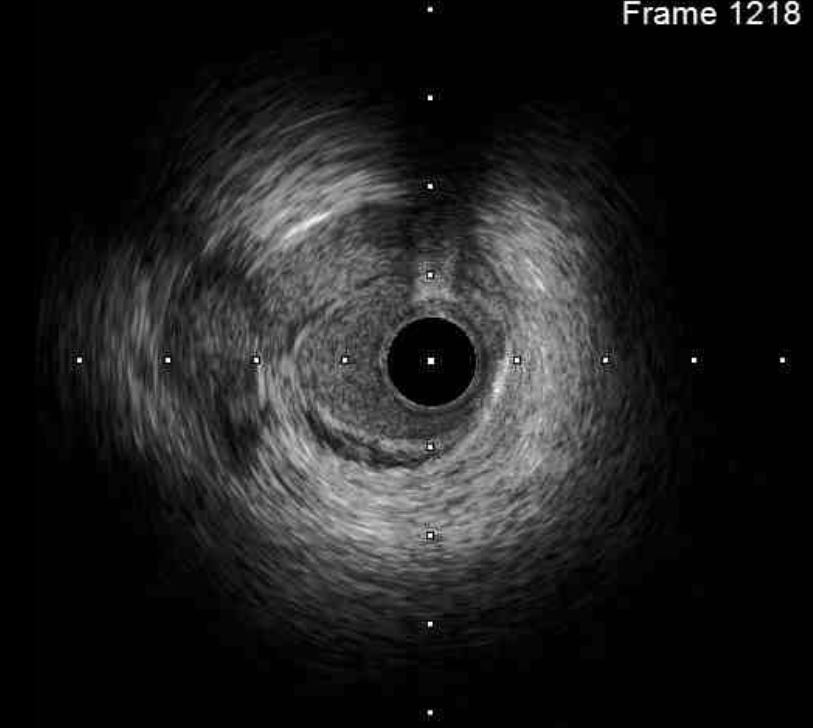

1st PCI for STEMI 1. The odd LAD lesion was checked by IVUS,revealing coronary dissection in mid LAD. 2. Angioplasty was performed with a 2.75*10mm Wolverine cutting balloon up to 8A10¡±, with fair LAD flow. --2nd PCI for recheck and unstable ECG findings 1. For dissection flap extending to distal LAD, wiring with a Sion wire was performed carefully. 2. Check IVUS to confirm true-lumen wiring and the extension of the dissection. Intimal flap and large burden of sub-intimal hematoma were noted. 3. Angioplasty with a 2.0*20mm balloon catheter, but with poor distal flow. 4. Long stenting to mid-to-distal LAD according to IVUS findings, with Onyx 2.0*26mm and Onyx 2.5*30mm 5. Angioplasty with a 1.5*20mm balloon catheter for distal run-off, 4A10¡± 6. Post-stenting dilatation with a 2.5*10mm balloon catheter, 4A10", low pressure considering the sub-intimal hematoma 7. Check final IVUS: The stents were well apposed. The proximal sub-intimal hematoma was not fully covered due to the vessel-size discrepancy. 8. The final flow was fair --3rd PCI for NSTEMI 1. For the un-reasonable rapid progression of the RCA lesion, I checked IVUS and coronary dissection was noted again. 2. No PCI was performed thereafter due to acceptable blood flow. --4th cath half years later The LAD was stationary and the RCA lesion was totally resolved.